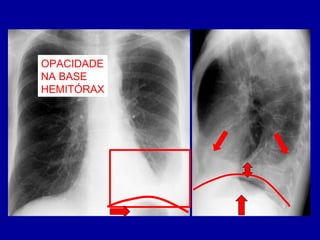

OPACIDADE

NA BASE

HEMITÓRAX

LESÃO PLEURAL

NÃO TEM PADRÃO

DE LÍQUIDO LIVRE